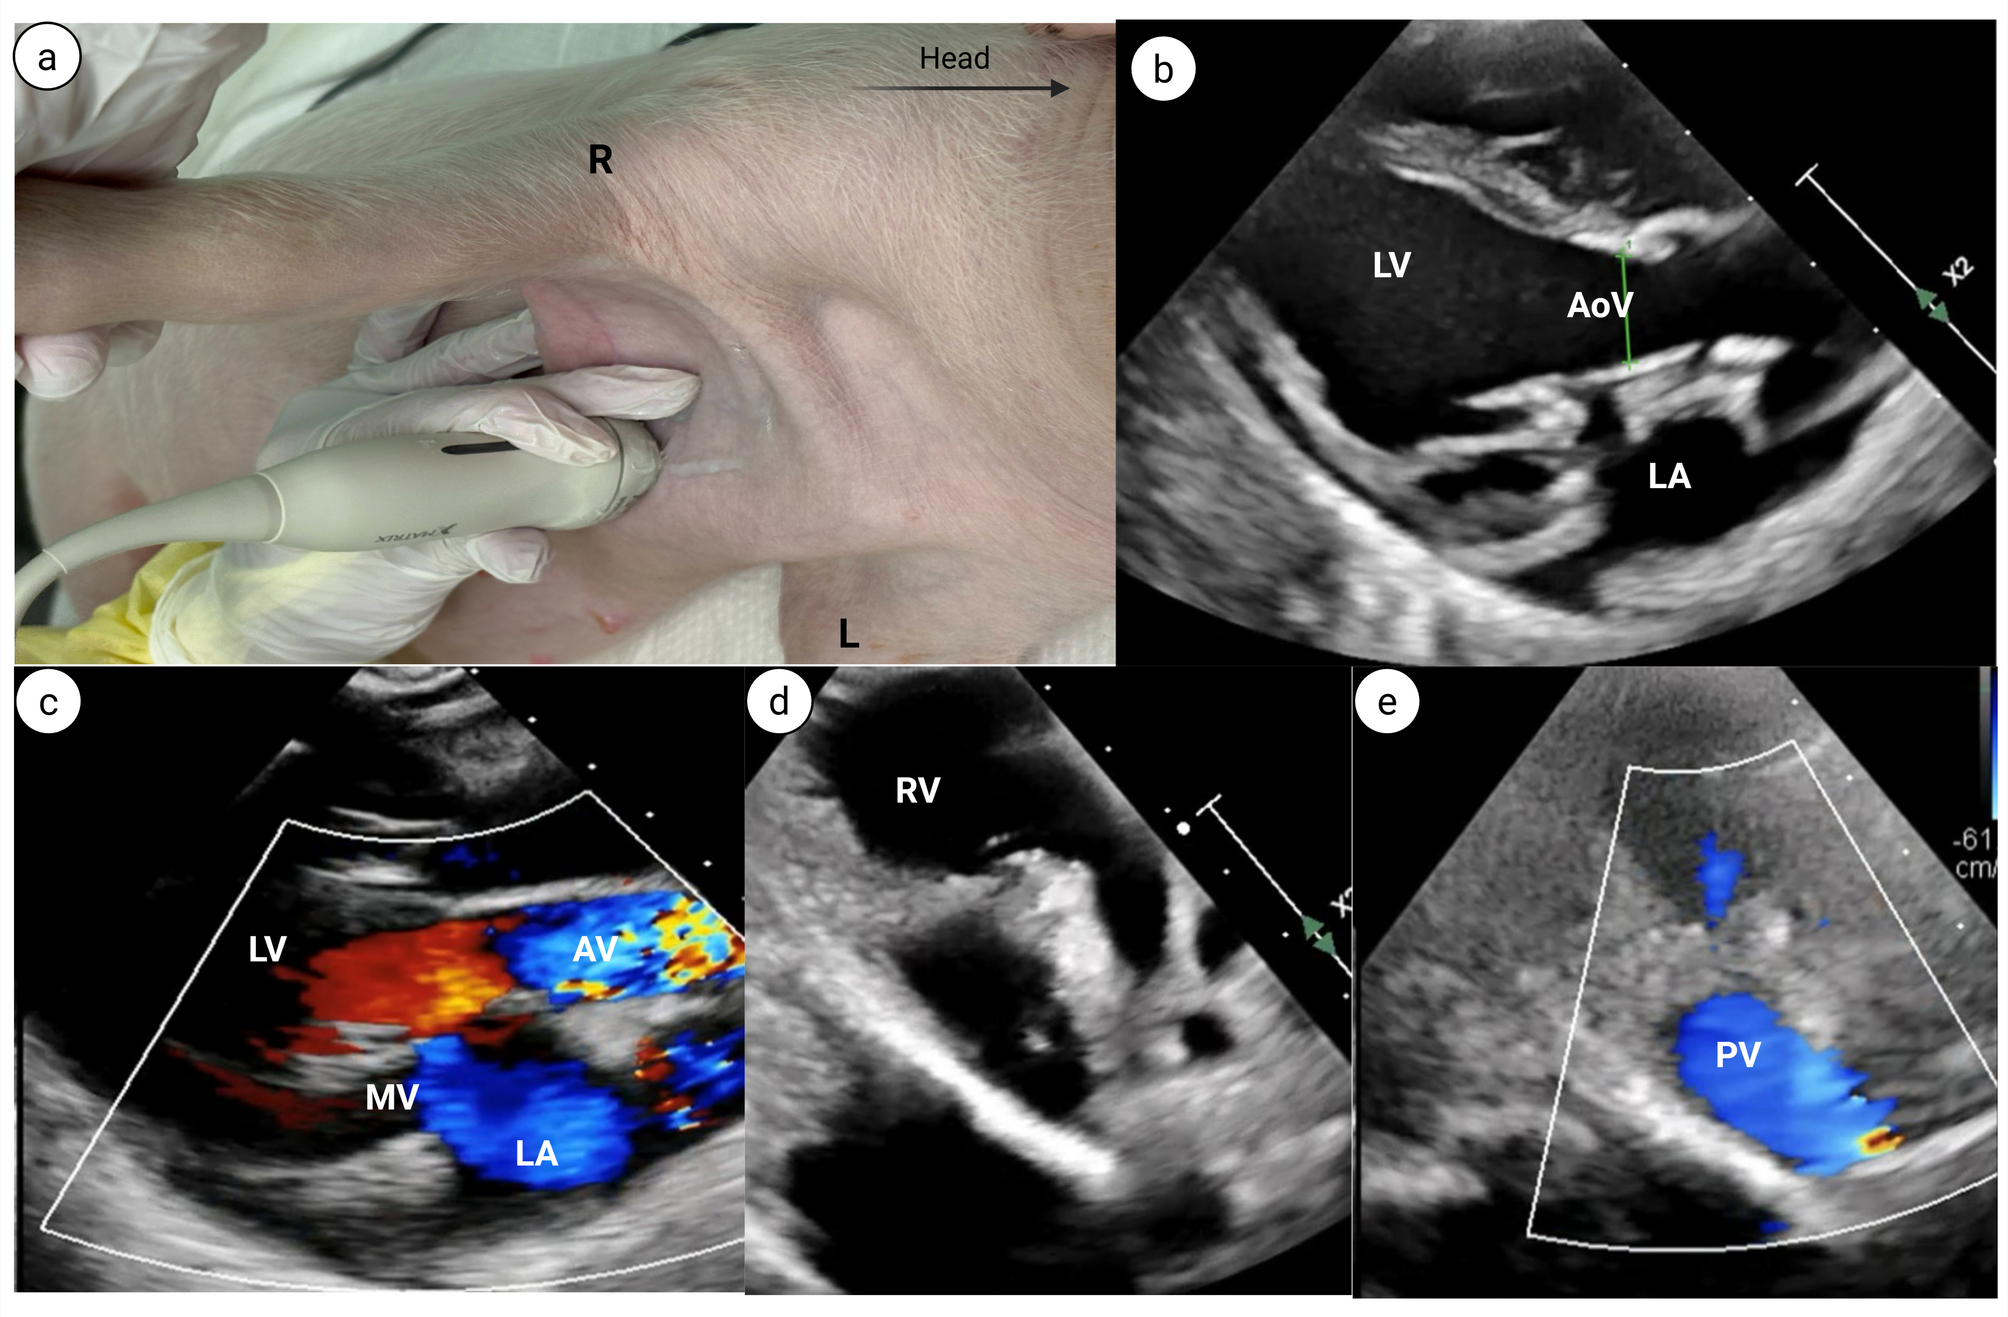

Fig. 4

Parasternal short axis (PSAX) view.